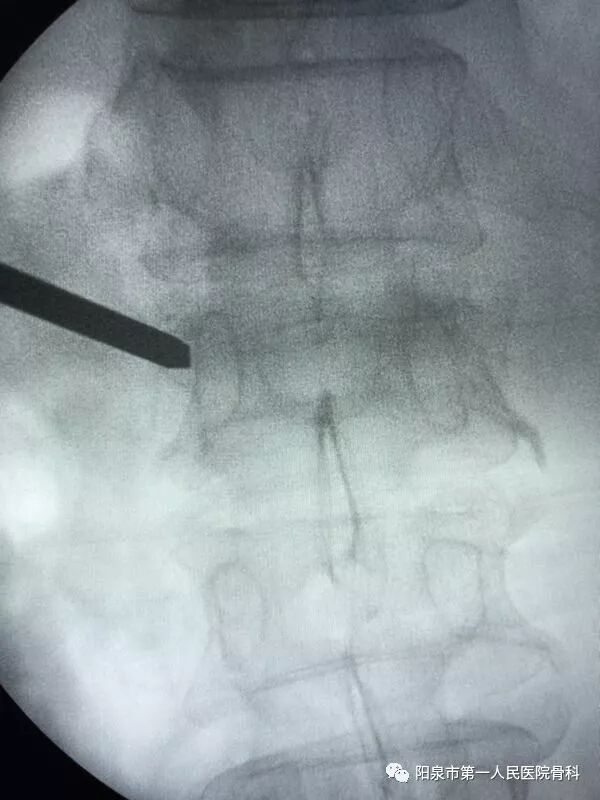

下面为在C臂机透视下观察到的穿刺操作过程,正侧位分别透视来确保正确的穿刺部位。图中黑色直杆为穿刺针。

椎体成型需要哪些器材椎体成形术概述_https://www.jmylbn.com_新闻资讯_第25张